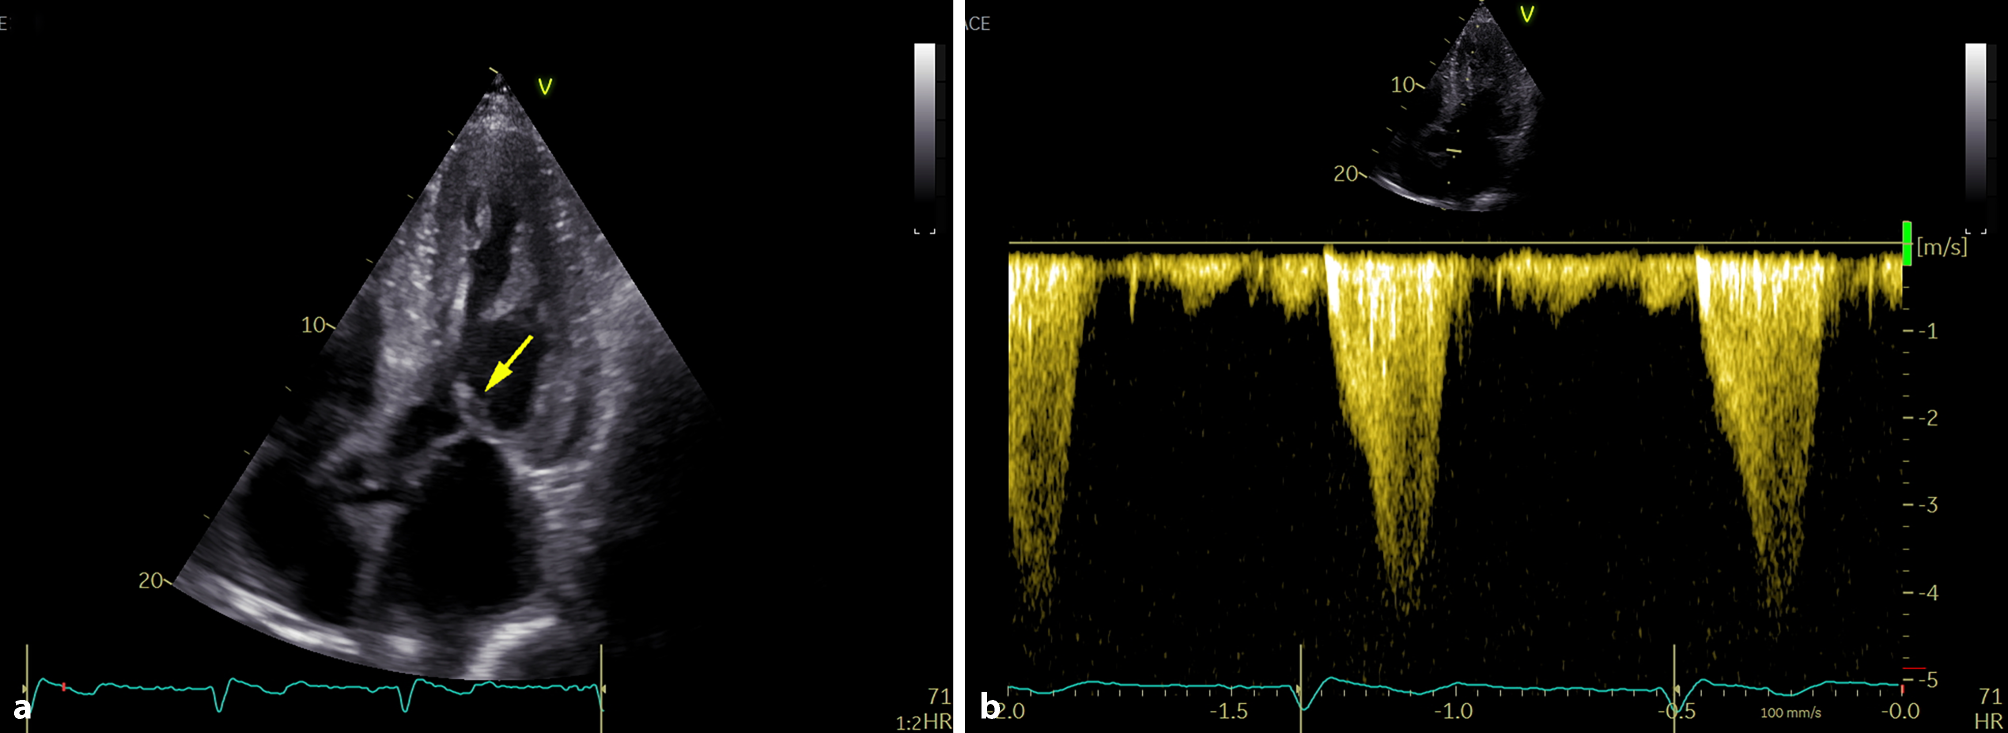

Fig. 3

Echocardiography: a apical five-chamber view demonstrating systolic anterior motion of the anterior mitral valve leaflet (yellow arrow) causing dynamic left ventricular outflow tract obstruction; b continuous wave Doppler tracing showing typical “dagger-shaped” velocity signal of dynamic left ventricular outflow tract obstruction with resting gradient of 70 mm Hg

During the first visit at our center in June 2023, the patient reported chronic shortness of breath consistent with functional class NYHA II, without any other symptoms of heart disease. His medications consisted of acetylsalicylic acid 100 mg once daily, clopidogrel 75 mg once daily, bisoprolol 5 mg daily, perindopril 5 mg daily and atorvastatin 20 mg daily. Blood pressure was 125/70 mm Hg, heart rate was 73 beats/min, respiratory rate was 16 respirations/min and oxygen saturation was 96% in room air. A holosystolic murmur at the left upper sternal border represented the main finding during the physical examination. Lung auscultation revealed clear breath sounds bilaterally. No signs of volume overload were present. An electrocardiogram (ECG) demonstrated sinus rhythm with first degree atrioventricular block and left anterior fascicular block. Laboratory tests did not reveal any significant abnormalities except for an elevation in NT-pro-BNP level (1137 ng/l) together with mild elevation of high-sensitive TnI level (51 ng/l). Echocardiographic examination confirmed the presence of pronounced concentric, diffuse LV wall thickening (septal thickness 17 mm, posterior wall thickness 15 mm, LV end-diastolic diameter 44 mm, relative wall thickness 0.68) with the absence of regional wall motion abnormalities and preserved LV ejection fraction of 71%, grade II diastolic dysfunction and left atrial dilatation. Global longitudinal strain was significantly reduced (−13.4%), with the relative apical sparing pattern (Fig. 2). Systolic anterior motion of the mitral valve leaflets was present causing significant dynamic LV outflow tract obstruction (LVOTO) with peak gradient of 70 mm Hg at rest (Fig. 3) and 140 mm Hg with a Valsalva manoeuvre. Due to this unexpected finding we decided to perform an endomyocardial biopsy for a definitive diagnosis of ATTR-CA. The biopsy revealed abundant extracellular amyloid deposits stained with Congo red. Subsequent immunohistochemical analysis demonstrated the presence of ATTR (Fig. 4). Additionally, myocyte hypertrophy and myocardial disarray were not present. The final diagnosis of cardiac ATTRwt1 was established after negative genetic testing excluding ATTRv. No pathogenic or likely pathogenic variant associated with sarcomeric HCM or Fabryʼs disease were found. Specific disease-modifying therapy with the transthyretin stabilizer tafamidis (61 mg per day) was initiated. Bisoprolol was increased up to 10 mg daily which led to resolution of the LVOTO and an improvement in functional capacity to NYHA class I.